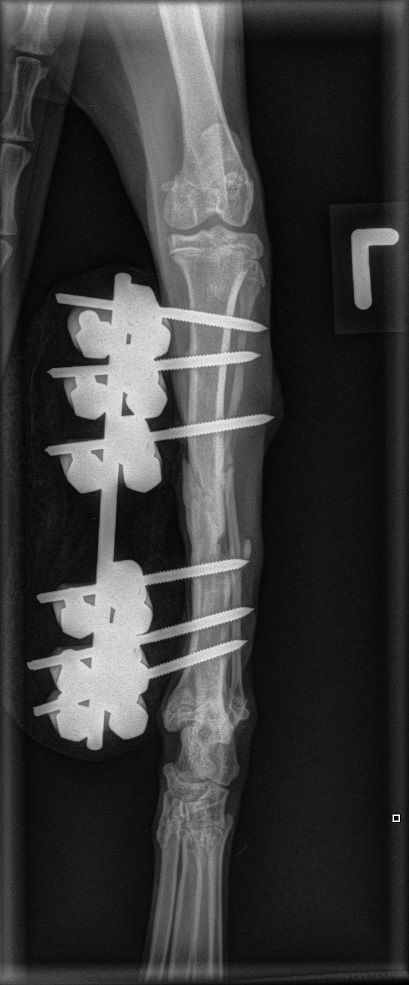

In der Folge operieren wir die Schienbeinfraktur der Katze mittels Fixateur Externe, pflegen das Tier während total 2 Monaten in der Praxis, nehmen mit fortgeschrittener Heilung eine Grundimmunisierung vor und kastrieren die Katze. Schlussendlich sind Schienbein- und Beckenbruch gut verheilt, und Ada kann mit einer leichten Lahmheit an eine Familienangehörige eines Praxisteam-Mitglieds weitervermittelt werden. Heute zeigt Ada keinerlei Lahmheit mehr, geniesst die Freiheit des Landlebens und veranstaltet Hindernisrennen mit den Kindern ihrer neuen Halterfamilie.